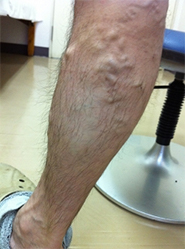

下肢静脈瘤

動脈は心臓から押し出された勢いで血液が流れていきますが、静脈にはそのような勢いがありません。筋肉の収縮と静脈に存在する逆流防止弁(一方弁)によって全身の組織から血液を心臓に戻します。その弁が種々の原因によって壊れてしまうことで、静脈血の逆流を引き起こし、静脈が瘤化していまったものを下肢静脈瘤と言います。軽症である無症状のものから、足がつりやすい、むくむ、痛いなどの症状を伴う中程度のもの、皮膚に湿疹や潰瘍ができる重症のものまであります。

当院では、最新式の下肢静脈瘤に対するレーザー治療機器ELVeSレーザー1470を使用しています。高周波治療でも治療効果はこの機器と同等と言われています。基本的には下肢静脈超音波検査、下肢単純CT撮影で手術適応、手術術式を決定しています。必要な場合には適宜検査を追加いたします。

治療法としては以下のものが考えられます。

• 弾性ストッキング:下肢の血液がうっ滞しないよう弾性ストッキングを着用します。

• 硬化療法:血管内に薬を注入し、瘤の拡大を防ぎます。

• 手術:弁が壊れてしまった静脈を抜去したり、静脈瘤を切除したりします。

• レーザー治療:静脈の内腔をレーザーにて閉塞させ、治療します。

2013年6月から、血管内レーザー治療を行っています。